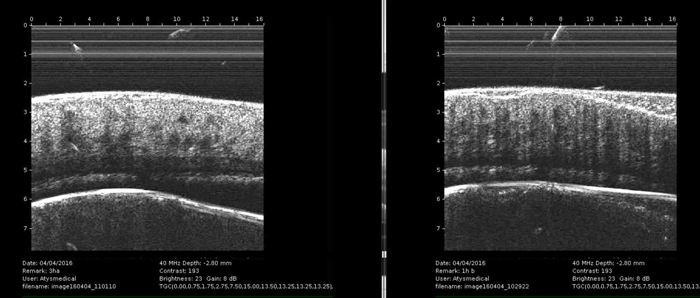

Στην πιλοτική αυτή εργασία διερευνήθηκαν οι μεταβολές των δομικών χαρακτηριστικών σε κλινικά υγιείς χοίρους διάφορων ηλικιών μιας εμπορικής χοιροτροφικής μονάδας στη Χαλκιδική. Σκοπός ήταν η αποτύπωση συγκεκριμένων μετρήσεων, ώστε να υπάρχει μελλοντικά το υπόβαθρο για συγκρίσεις με ασθενή ζώα.

Η αποτύπωση αυτή έγινε με τη χρήση εξειδικευμένης φορητής διάταξης υπερήχων με συχνότητες λειτουργίας 32-40 και 50ΜΗz σε σχετικά σταθερά δομικά στοιχεία και συγκεκριμένα στο κρανίο και το μετατάρσιο χοίρων ηλικίας 10, 25 και 50 ημερών. Όπως εξηγούν οι καθηγητές της Κτηνιατρικής, Σπύρος Κρήτας και Ιωάννης Γρίβας, η καλή υγεία των ζώων αντανακλάται στην καλή απορρόφηση και αξιοποίηση θρεπτικών συστατικών και, επομένως, της ορθής δομής του οργανισμού. Αυτή η δομή διαταράσσεται σε περιπτώσεις παρουσίας λοιμωδών, παρασιτικών και μεταβολικών νοσημάτων. Η γρήγορη ανίχνευση τέτοιων δομικών διαταραχών θα δώσει μια κατ’ αρχήν πληροφορία για τη μετέπειτα πορεία και περισσότερο εξειδικευμένη διερεύνηση, σε ό,τι αφορά την υγεία των ζώων. «Μετράμε με τη μέθοδο του μη επεμβατικού ελέγχου και σε σημεία που έχουμε προκαθορίσει, εάν το πάχος του ιστού είναι το ίδιο με ένα υγιές ζώο. Εάν δεν είναι, γιατί μπορεί να έχει ένα λοιμώδες νόσημα, τότε το ζώο δεν μπορεί να απορροφήσει καλά την τροφή, οπότε δεν θα έχει ασβέστιο ή άλλα συστατικά στον ίδιο βαθμό που θα έχει ένα υγιές ζώο», διευκρινίζει ο κ. Κρήτας.

Στην αρχή της ανάπτυξης του οργανισμού, τα μηχανικά χαρακτηριστικά των οστών είναι αρκετά όμοια με τα μηχανικά χαρακτηριστικά των υπερκείμενων ιστών. Με την πάροδο της ηλικίας, όμως, οι μηχανικές ιδιότητες των οστών διαφοροποιούνται δραματικά σε σχέση με αυτές των υπερκείμενων οστών. Αυτή η διαφοροποίηση αναδεικνύει τόσο την ποιότητα της τροφής που παρέχεται όσο και την ποιότητα της υγείας των ζώων, λαμβάνοντας πάντα υπόψη ένα περιοδικό σύνολο μετρήσεων κατά την αρχική ανάπτυξη. Με τον συγκεκριμένο υπέρηχο και τον έλεγχο των προκαθορισμένων σημείων διερευνάται η υγεία των ζώων και, κατ’ επέκταση, η παραγωγικότητά τους.